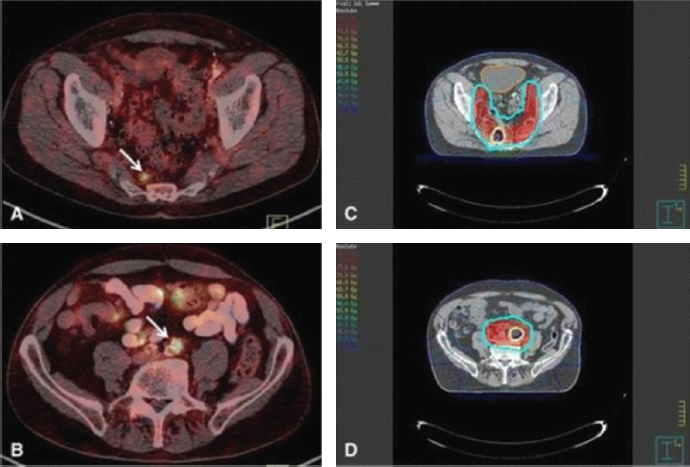

На рис. 5 и 6 представлены сцинтиграммы результатов КИ с 99mTc-PSMA, полученные методом ОФЭКТ/КТ с высокой диагностической эффективностью при визуализации метастатического РПЖ [24].

Рис. 5. Проекция максимальной интенсивности (справа) и совмещённые с КТ (слева) 99m Tc-HYNIC-PSMA ОФЭКТ/CT изображения пациента 59 лет, ранее перенёсшего радикальную простатэктомию, через 2 часа после введения дозы 740 МБк. Были обнаружены множественные метастазы в лимфатические узлы (обозначены стрелкой), а в левом надключичном лимфатическом узле максимальное отношение опухоли к фону составляет 9,2 / Fig. 5. Maximum intensity projection (right) and 99m Tc-HYNIC-PSMA SPECT/CT superimposed with CT (left) images of a 59-year-old patient who had previously undergone radical prostatectomy, 2 hours after a dose of 740 MBk. Multiple lymph node metastases were found (indicated by an arrow), and in the left supraclavicular lymph node, the maximum tumor-to-background ratio is 9.2

Рис. 6. 99mTc-PSMA: два очага активности в малом тазу (белые стрелки); неспецифическое поглощение (контурные стрелки); точная локализация очагов на совмещённых ОФЭКТ/КТ изображениях (нижний ряд) / Fig. 6. 99mTc-PSMA: two foci of activity in the small pelvis (white arrows); nonspecific uptake (outline arrows); exact localization of lesions on combined SPECT/CT images (bottom row)